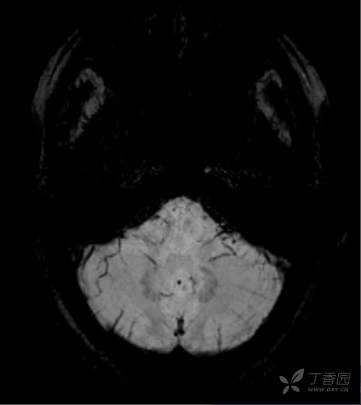

颈部、脑部动脉均未见明显异常,MRI+MRA+T2Flair+SWI+冠状位: 双侧额顶叶皮层下散在小缺血灶;双 侧海马萎缩2级,小脑蚓部、右侧额 叶微出血灶,如下图所示: